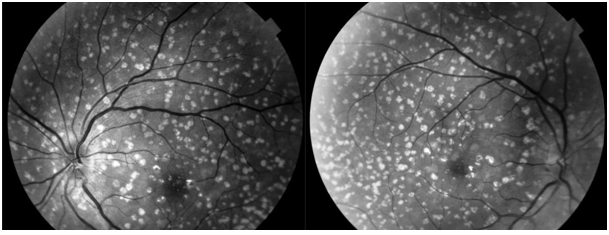

Drusen are yellow or white accumulations of extracellular material made up of lipids and proteins that build up between basal blade of retinal pigment epithelium and collagen layer of Bruch’s membrane. They are the most common clinical manifestation of aging and usually occur in the population over 50 years old, however a special entity may occur earlier, especially Large Colloid Drusen.1,2 Large Colloid Drusen most often develops in women with no family history of retinopathy, with a low risk of choroidal neovascularization or significant loss of visual acuity.3 We report the case of a 45 years old female patient, with no prior ophthalmological or general history, who presented to the consultation for decreased near visual acuity. The far visual acuity was 20/20 OU without correction, examination of the anterior segment was normal. At the Fundoscopy: Large bilateral lesions, yellowish under retinal from the posterior pole to the mid-periphery(Figure 1), without reaching the extreme retinal periphery (Figure 2). Fluorescein angiography objected: hyperfluocescence in early and late times (Figure 3). Macular OCT: Convex shaped drusen with homogeneous internal hyper-reflectivity, and attenuation of the ellipsoid zone in relation without reaching the fovea (Figure 4).

Figure 1 Large bilateral lesions, yellowish under retinal from the posterior pole to the mid-periphery.